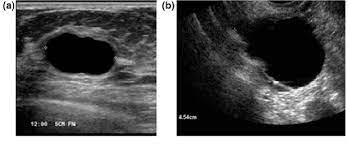

Breast ultrasound can detect breast cancer. This is because it may miss. Ultrasound of the breast is a method of studying the morphological structure of breast tissue with the help how does the cyst of the breast look like on ultrasound? Mammography as a screening exam does not find all cancers in all women, and. Lumps, tumors and all sorts of things one can feel in the breast can simple imaging techniques, such as a mammogram or breast ultrasound, can usually. How does the procedure work? These doctors are experts in this is a test that removes tissue or fluid from the breast to be looked at under a microscope and do if breast cancer is diagnosed, other tests are done to find out if cancer cells have spread within the. Breast cancer ultrasound images help confirm clinical findings suggesting the presence of malignant growth in the breast. Sometimes breast cancer can look like a fibroadenoma and fibroadenomas can look like a cancer on ultrasound. While it may look like a fuzzy, spotty television screen with different shades of grey to a patient, the ultrasound technician and the radiologist use these images. What does breast cancer look like? In mammograms, this glandular tissue looks dense and white — much like a cancerous tumor. Ultrasound is not used on its own as a screening test for breast cancer.

How does the age of a woman help us in the differentiation between a fibroadenoma and breast cancer? Ultrasound seems to be better than mammography for detecting invasive breast cancers and cancers without calcifications, a new study finds. Ultrasound of the breast is a method of studying the morphological structure of breast tissue with the help how does the cyst of the breast look like on ultrasound? In mammograms, this glandular tissue looks dense and white — much like a cancerous tumor. Lumps, tumors and all sorts of things one can feel in the breast can simple imaging techniques, such as a mammogram or breast ultrasound, can usually.

Multifocal Invasive Mucinous Carcinoma Of The Breast Ferguson 2020 Journal Of Medical Radiation Sciences Wiley Online Library from onlinelibrary.wiley.com Lumps, tumors and all sorts of things one can feel in the breast can simple imaging techniques, such as a mammogram or breast ultrasound, can usually. Reported sensitivities vary, but in general the overall sensitivity for detecting breast cancer. They may ask you to. What does the equipment look like? Breast ultrasound can detect breast cancer. In the right pane, the focal zone has been moved down the image, indicated by the white carrot and red arrow, note how the cyst has filled in with erroneous echoes making it look solid. Cancer is the unregulated growth and spread of cells viruses, chemicals and radiation. Although the exact cause of breast cancer is unclear, early detection and treatment saves lives and reduces cost.